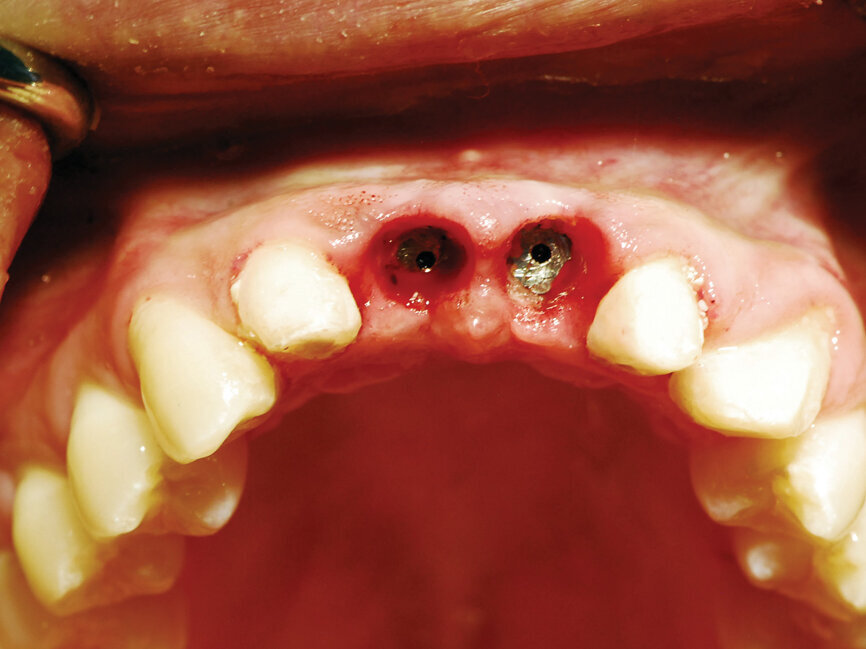

Six months post-implant placement, the provisional bridge was removed and preservation of the papillas was confirmed with a natural emergence profile within soft tissue (Figs. 6,7). Local anesthetic was administered. The Picasso Lite+ diode laser was set at 2.5 watts in continuous mode with an initiated tip and at the center of the depression in the soft tissue above the implants cover screw and moved in a circular motion moving outward until the entire cover screw was exposed (Fig. 8).

The process cuts the desired soft tissue and coagulates any bleeding from the cut edges. This was then repeated on the second implant (Fig. 9). Open tray implant impression abutments were placed into the implants and seating verified radiographically. An impression of the maxillary arch was taken utilizing Aquasil heavy body VPS (Dentsply Sirona, Milford, Del.) in a Mira Advanced Implant tray (Hager Worldwide, Hickory, N.C.) and Aquasil Ultra syringed around the preparations and implant abutment heads.

Fig. 8: Picasso Lite+ diode laser removing soft tissue to uncover the implants’ cover screws. (Photo provided by Dr. Gregori M. Kurtzman)